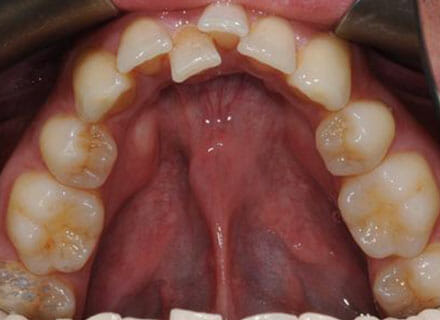

In this case, we needed to reduce the size of the central incisors as they were just too big. This combined with the crowding at the front had caused the lateral incisors to become trapped inside, pushing the big central incisor teeth forwards even more. After reducing the big teeth to a normal size we started with fixed clear bracket brace treatment and were able to complete this case in a little over a year.